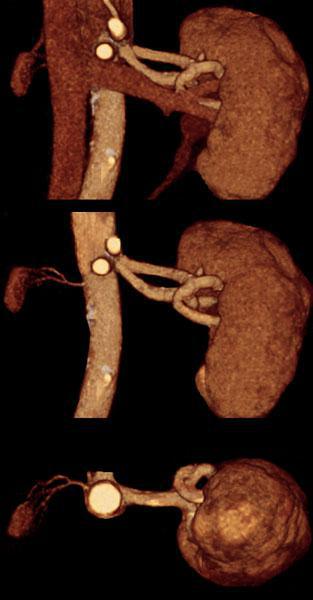

Hipoplasia renal 1

Hipoplasia renal 2